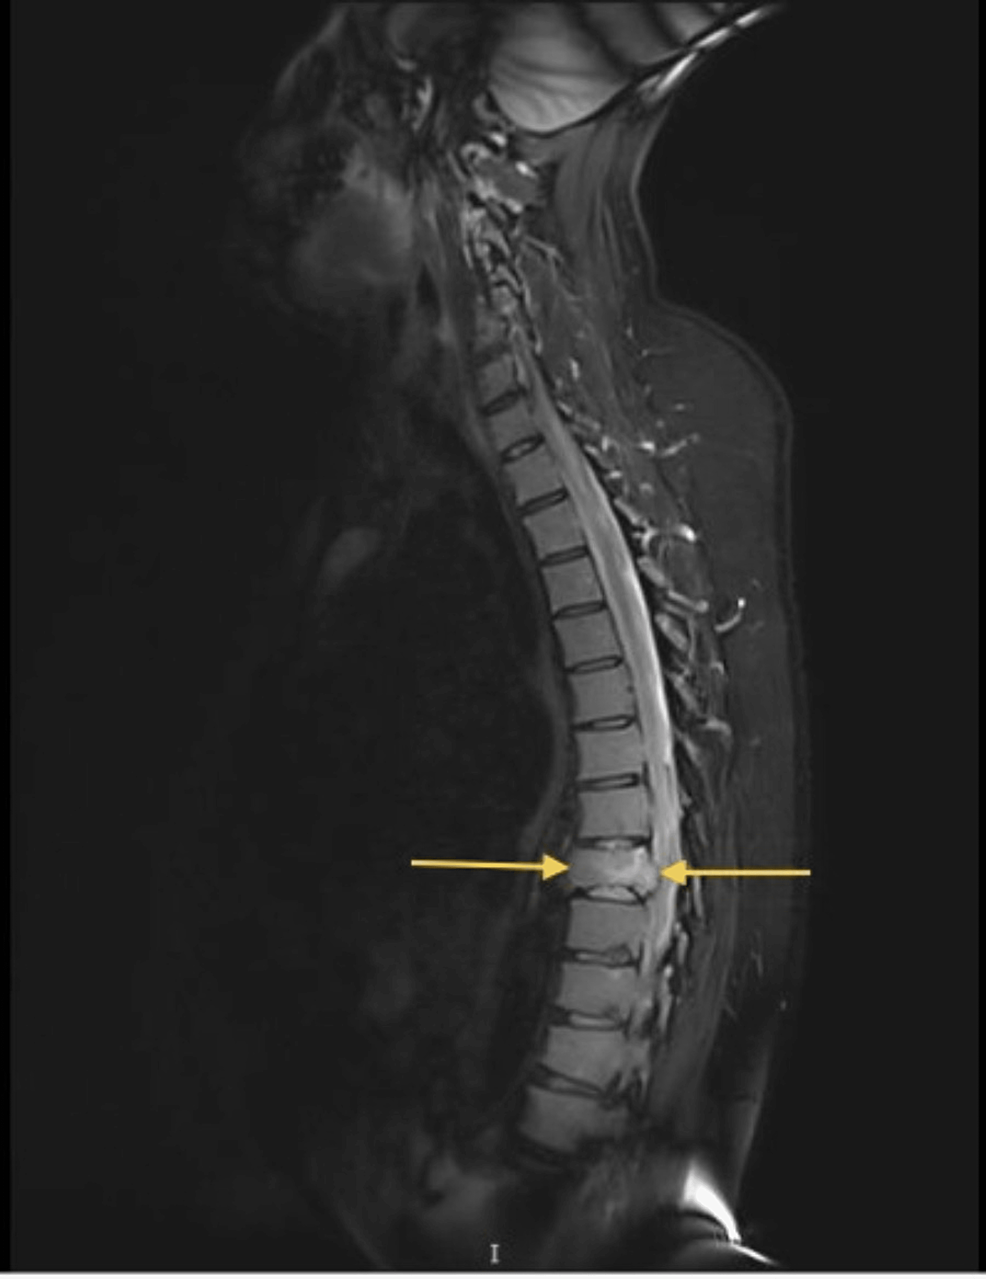

MRI of the patient showing multilevel vertebral compression fractures Spinal Compression Fracture Multiple Myeloma Vertebral compression fractures (vcfs) are the most common type of fractures in patients with mm. The presence of edema on mr imaging is a common finding in acute or subacute vertebral body compression fractures. Radiotherapy is recommended for uncontrolled pain, impeding or symptomatic spinal cord compression, or pathological fractures. What are spinal fractures and vertebral compression fractures, why do they. Spinal Compression Fracture Multiple Myeloma.

Spinal Compression Fracture Multiple Myeloma The presence of edema on mr imaging is a common finding in acute or subacute vertebral body compression fractures. If some of the bones in the spine (vertebrae) are weakened by the myeloma, they may collapse. Surgery should be used for the. What are spinal fractures and vertebral compression fractures, why do they occur, and what. This multiple myeloma cancer publication discusses how myeloma patients can manage vertebral compression fractures. Spinal cord compression (scc) is a devastating complication of multiple myeloma and has the potential to cause loss of. This infoguide covers key questions and topics about spinal fractures in myeloma, including: Vertebral compression fractures (vcfs) are the most common type of fractures in patients with mm. It can be overwhelming to read about complications of myeloma, like spinal fractures (also known as vertebral compression. Radiotherapy is recommended for uncontrolled pain, impeding or symptomatic spinal cord compression, or pathological fractures. Vcfs are known to occur at. This called a compression fracture. The presence of edema on mr imaging is a common finding in acute or subacute vertebral body compression fractures.

Spinal Compression Fracture Multiple Myeloma . This infoguide covers key questions and topics about spinal fractures in myeloma, including: Surgery should be used for the. Vertebral compression fractures (vcfs) are the most common type of fractures in patients with mm. It can be overwhelming to read about complications of myeloma, like spinal fractures (also known as vertebral compression. If some of the bones in the spine (vertebrae) are weakened by the myeloma, they may collapse. What are spinal fractures and vertebral compression fractures, why do they occur, and what. Vcfs are known to occur at. This multiple myeloma cancer publication discusses how myeloma patients can manage vertebral compression fractures. Spinal cord compression (scc) is a devastating complication of multiple myeloma and has the potential to cause loss of. The presence of edema on mr imaging is a common finding in acute or subacute vertebral body compression fractures. Radiotherapy is recommended for uncontrolled pain, impeding or symptomatic spinal cord compression, or pathological fractures. This called a compression fracture.